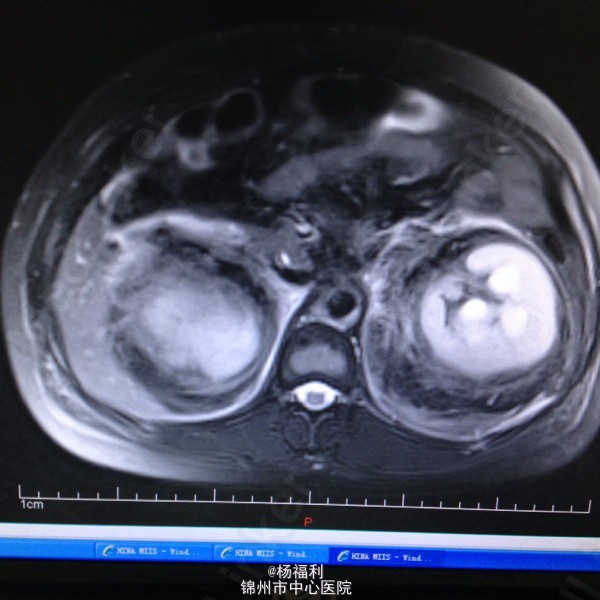

44岁女患。为消化科我会诊患者。 现病史:以上腹痛9小时为主诉入院。无发热及寒战、噁心未呕吐,无腹泻及黑便。 既往史:双眶炎性假瘤2年,口服激素治疗,并补钾。

查体:上腹部压痛,无反跳痛、右侧压痛明显,右肾区叩击痛,左肾区轻叩击痛,双输尿管走形区无压痛。 辅助检查;泌尿系彩超:双肾积水。 血白细胞:9.99*10^9。 肾功能正常。 全腹部ct及MRU检查:见图片。

诊断;真的不知道是啥病。 处理:暂时止痛处理。双肾病变。不知从哪里下手。